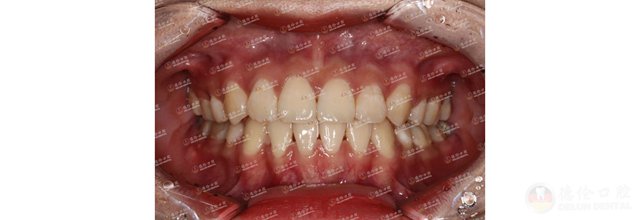

魏女士因牙齿不齐,笑起来不太自信,甚至不愿意笑,想一解烦恼的魏女士选择了德伦口腔东风总院正畸科副主任王苏静进行正畸治疗。嘴凸、牙不齐、薄龈型、且根形明显,王主任在详细检查过魏女士牙齿情况后为其设计了金属自锁的正畸方案,魏女士加入矫牙变美的道路。

魏女士看着自己的牙齿逐渐变得整齐好看,笑起来越来越自信了。回顾矫牙前的自己,笑容始终有一丝放不开,如今在王主任的正畸技术下牙齿逐渐变得整齐,自己的脸型也逐渐变美。

历经23个月,魏女士终于成功“毕业”!魏女士对王主任心怀感激,特意献上一面锦旗,虽然这只是一面简单的锦旗,但这面锦旗饱含的是魏女士心中对王主任的感谢与爱。